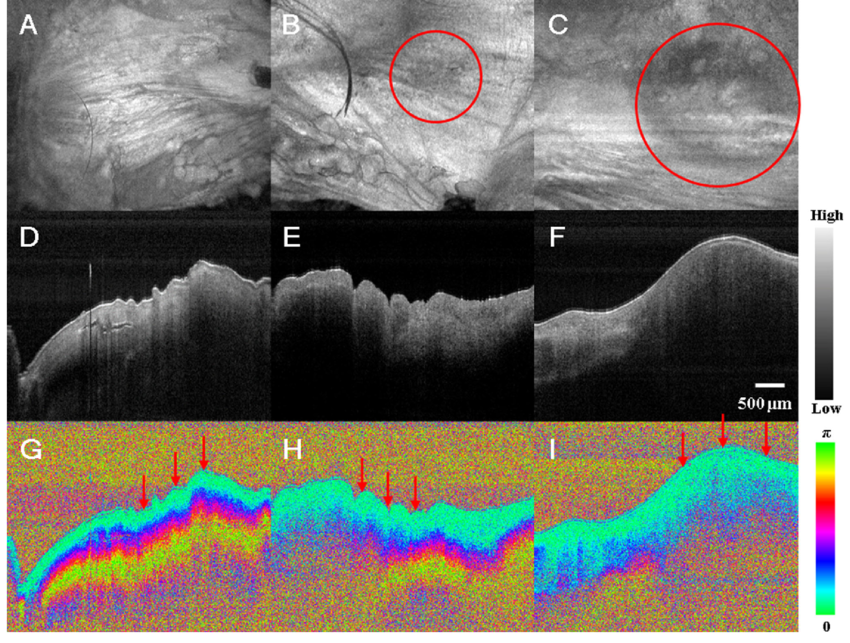

PS-OCT 通过检测组织的双折射性、相位延迟及偏振退偏程度,反映胶原、肌纤维、髓鞘等取向结构。该技术在角膜胶原结构评估、皮肤纤维化诊断及牙釉质损伤检测中具有重要应用。

9. Zhou, X., Won, K. S., Chulho, O., Young, K. D., Hyuk, C. J., Yong, K. T., ... & Yeh-Chan, A. (2021). Investigation of the Clinical Potential of Polarization-Sensitive Optical Coherence Tomography in a Laryngeal Tumor Model. 조직공학과 재생의학, 18(1), 81-87.